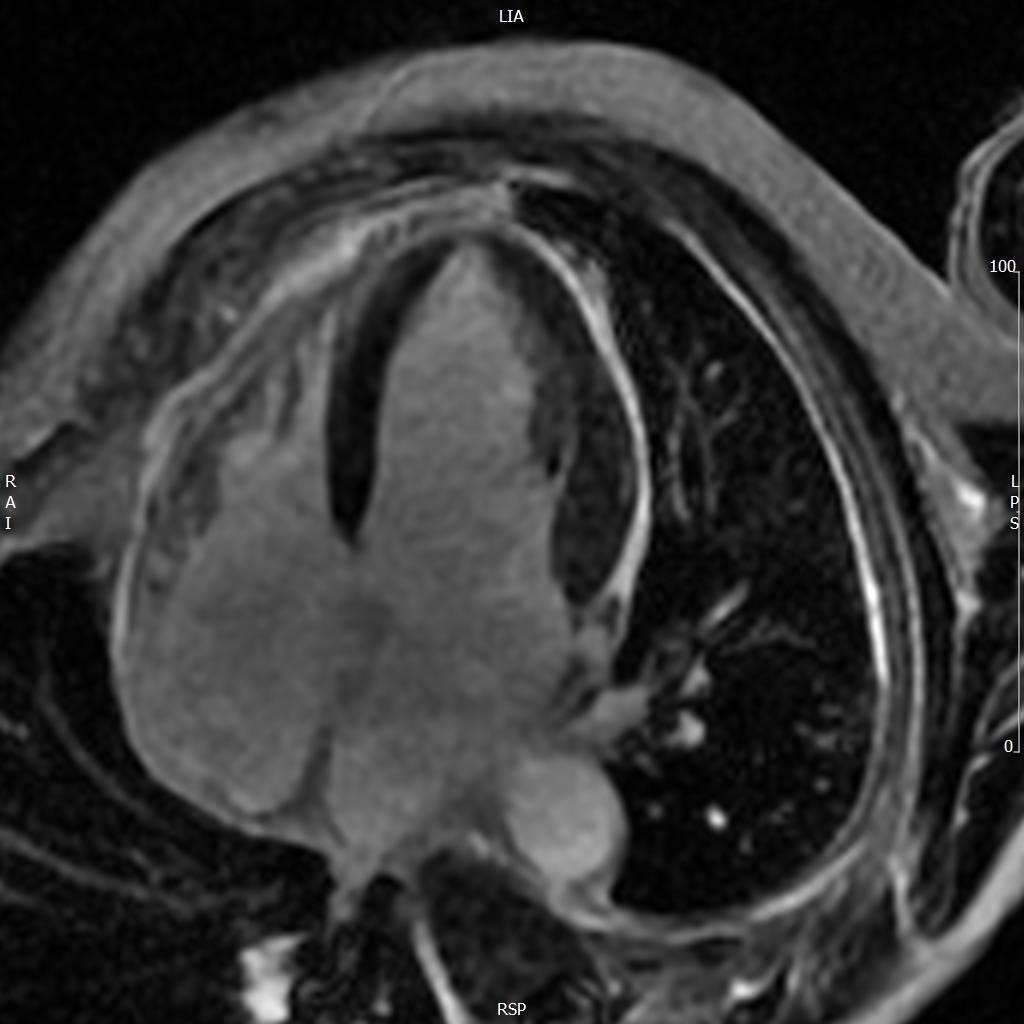

A 52-year old man with a history of diffuse large B cell lymphoma in remission presented with 3 weeks of shortness of breath, cough, fever, and shock. Electrocardiogram revealed sinus tachycardia, diffuse ST segment elevations, PR segment depression, prolonged QTc, and electrical alternans. Bedside echocardiogram was performed, revealing a large circumferential pericardial effusion with tamponade physiology. The patient underwent echo-guided pericardiocentesis with drainage of 400 ml of purulent fluid. Pericardial and blood cultures were positive for Haemophilus influenzae. A CT of the chest was indicative of empyema. Given the patient’s history of rituximab use, autologous stem cell transplant, and profound infection, immunoglobulin levels were drawn and found to be undetectable. The patient received 6 weeks of intravenous antibiotics with IVIG infusions. He was treated with colchicine and aspirin for purulent pericarditis. Two months later, a cardiac MRI was performed, which revealed resolution of the pericardial effusion. No evidence of constrictive pericarditis was noted on MRI, but continued pericardial enhancement was observed. Colchicine was continued for an additional 3 months. The patient made a full recovery at 6 month follow up.